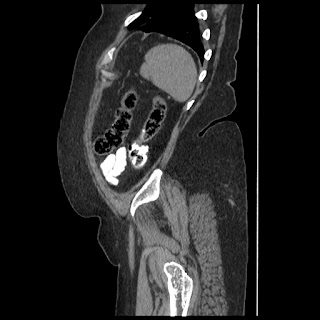

A 70 years old woman with Obstractive jaundice & palpable GB